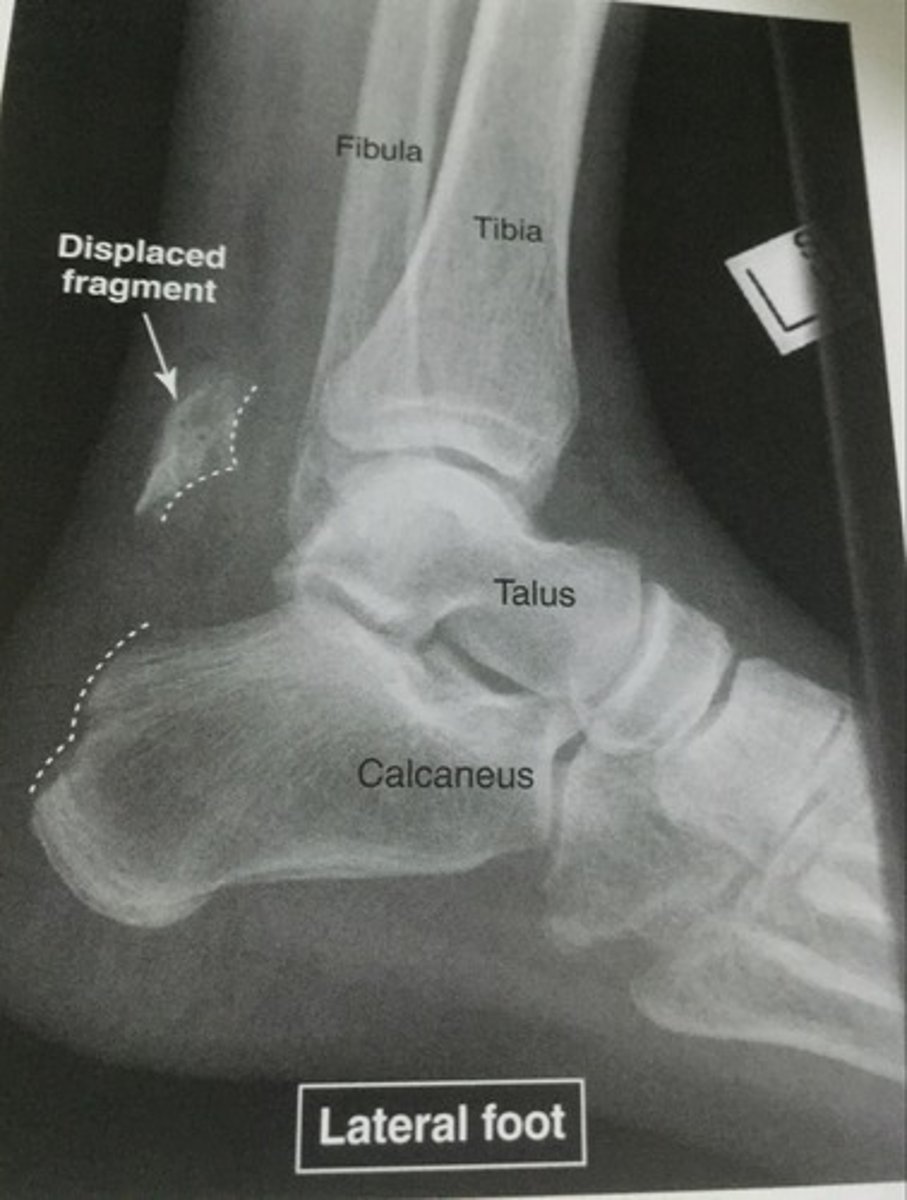

avulsion fracture

Fracture due to tendon/ligament pulling off small piece of bone